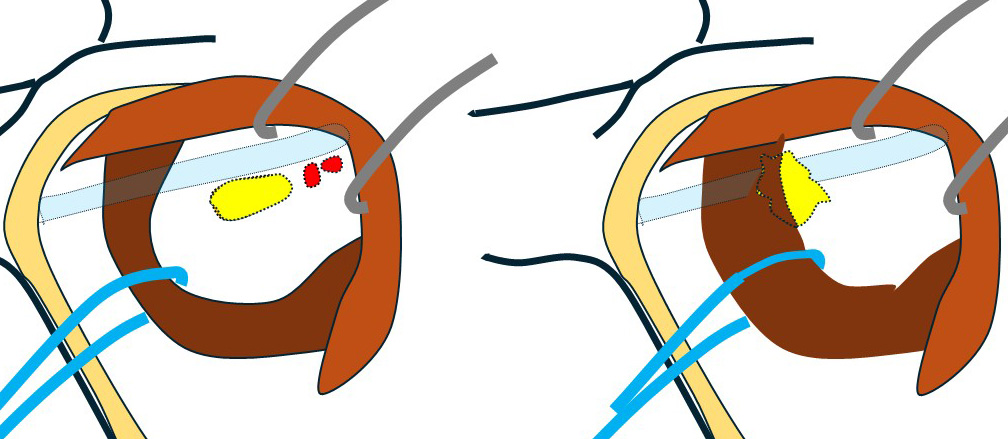

向かって左が「コラム540症例」 右が今回の症例となります。

通常の腋窩郭清(小胸筋内縁まで)の視野です。

鎖骨下リンパ節(レベルⅢ)は「小胸筋の向こう(奥)」にあるので『小胸筋を何とかしなくては』そこへはアプローチできません。

殆ど(ほぼ全て)の乳腺外科医は、ここまでで(小胸筋を何ともすることもできず)終了となります。

〇この先が「鎖骨下郭清」となります。

通常であれば

このように… 小胸筋にテーピングをして

手前に引っ張り出せば図左のように鎖骨下リンパ節が「ばっちり」鎖骨下静脈と離れて認識できます。

これ(向かって左の図)が「コラム 540回目症例」であり、それであれば「何てこともない」のですが…

向かって右に見える「今回の症例」は(小胸筋を引っ張っても)節外浸潤した鎖骨下リンパ節が(エコーで想像した通り)鎖骨下静脈に(恋人たちのように)ぴったりと寄り添って離れない!

鎖骨下リンパ節が鎖骨下静脈から外せない。この視野で無理やり剥がそうとすれば…(考えたくもない)